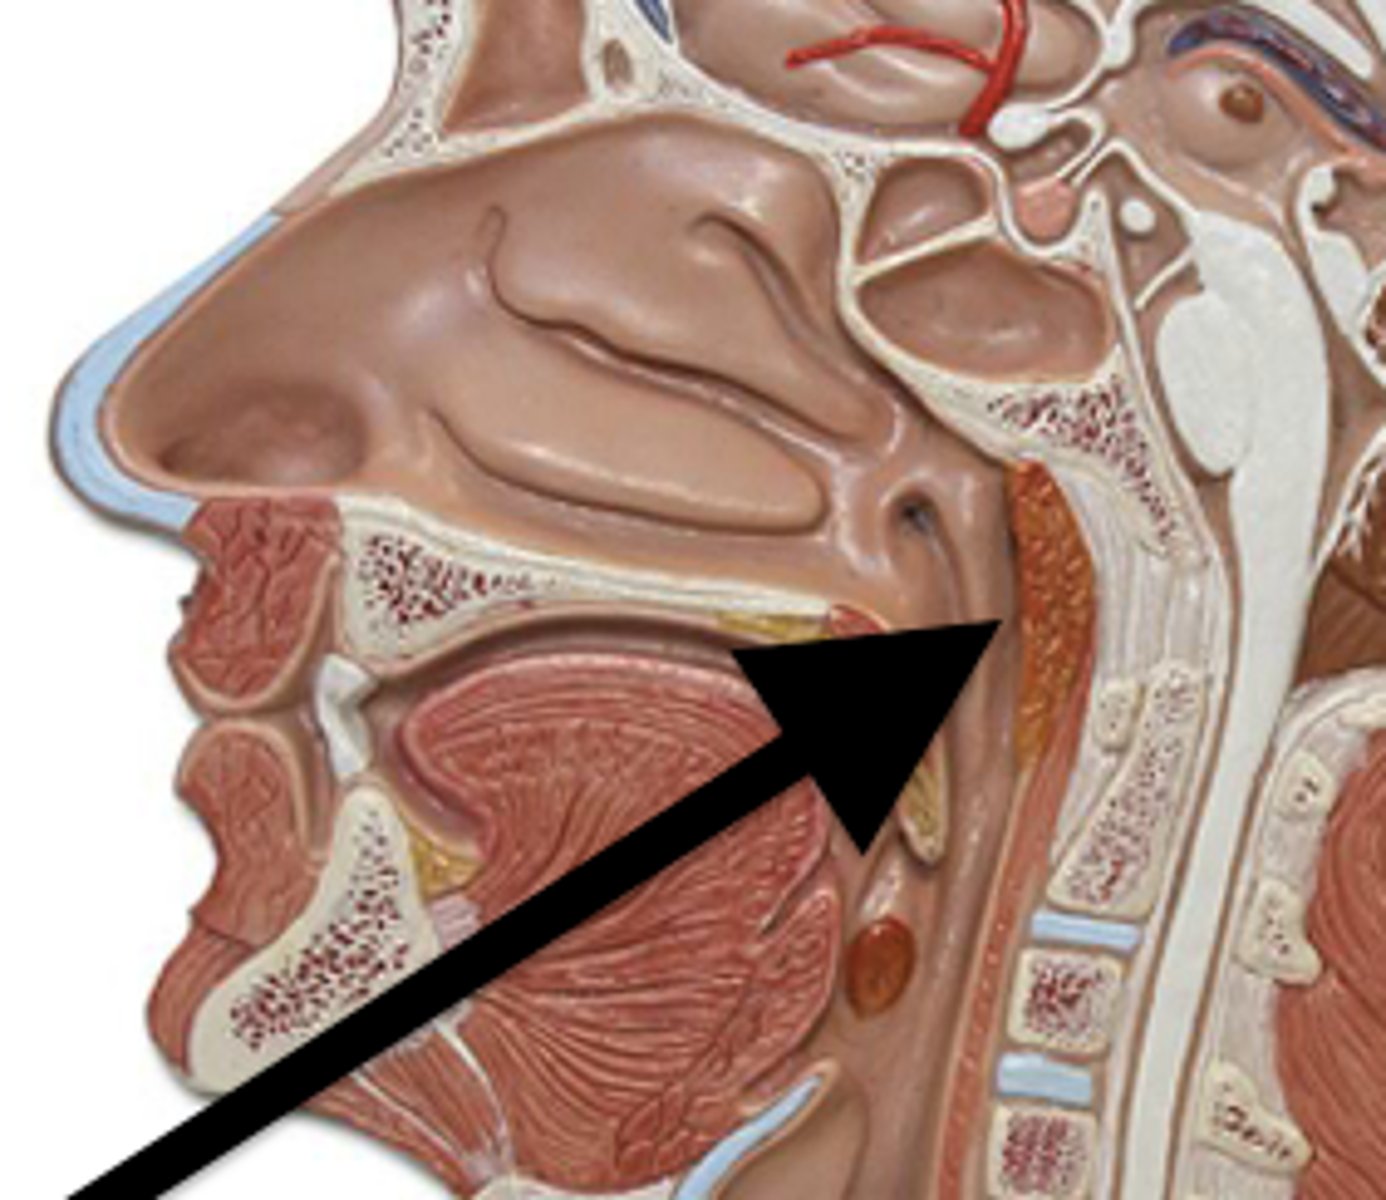

Nose

Organ of smell

Nasal Cavity

Hollow space behind the nose

Turbinates (Conchae)

- Bones that protrude into the nasal cavity- that increases surface area for filtering dust and dirt particles by the mucous membrane

- There's an inferior, middle, and superior one (2.), 3.), 4.))

Olfactory Region

A dime-sized area at the top of each nasal cavity that houses sensors responsible for smell (1.))

Hard (Bony) Palate

Anterior palate portion that is supported by the palatine processes of the maxillae and the palatine bones (8.))

Meatuses

- Constricted passageways in the nasal cavity that produce air turbulence

- There's an inferior, middle, and superior one

(5.), 6.), 7.))

Soft Palate

Posterior palate portion, not supported by bone (9.))

Paranasal Sinuses

- Frontal

- Ethmoid

- Sphenoid

- Maxillary

Frontal Sinus

Cavity within the frontal bone (yellow)

Ethmoid Sinus

Mucosa lined air spaces located above the sphenoid sinus and below the frontal sinus (purple)

Sphenoid Sinus

Sinus above and behind the nose (green)

Maxillary Sinus

Sinus on either side of the nasal cavity below the eyes (pink)

Functions of the Nose

Nasopharyx

The portion of the pharynx that extends from the nostrils to the soft palate

Oropharynx

Central portion of the pharynx between the roof of the mouth and the upper edge of the epiglottis